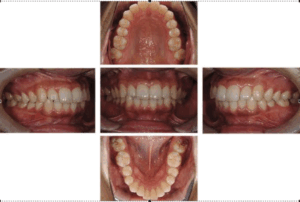

口腔内写真

これは、口腔内の疾患を診査診断するための資料となります。

この資料があると、治療部位の説明や口腔内の状態を記録し経年的な変化を観察できます。